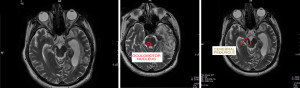

We present a case involving a 46-year-old man admitted to the Neurorehabilitation Unit following a severe traumatic brain injury (TBI) due to an accidental fall at home. All procedures performed in this study were in accordance with the ethical standards of the institutional and/or national research committee(s) and with the Declaration of Helsinki and its subsequent amendments. Written informed consent was obtained from the patient for publication of this case report and accompanying images. A copy of the written consent is available for review by the editorial office of this journal. Two months earlier, the patient had sustained a head injury resulting in an acute epidural hematoma on the left side, leading to a coma characterized by bilateral mydriasis and decerebrate posturing. He underwent emergency surgery to evacuate the hematoma, followed by a tracheostomy. After surgery, he remained in a comatose state, and was transferred to our unit for rehabilitation. Upon admission, his condition included occasional right eye opening and signs of a left third cranial nerve deficit. His responses were minimal, characterized by limb flexion, and he was breathing on his own through a tracheostomy tube. Initial computed tomography (CT) scans showed a reduction in brain swelling and signs of ex vacuo dilation, indicating brain tissue loss. A magnetic resonance imaging (MRI) performed later revealed areas of gliosis and necrosis in the left temporal and occipito-parietal regions and the right cerebral peduncle (Figure 1), reflecting widespread bilateral brain damage. Functional evaluations showed that brainstem auditory responses were normal, but cortical sensory responses were significantly reduced on the left side, suggesting an imbalance between brainstem and higher cortical processing. During the early stages of speech therapy, the patient was unresponsive, with eyes closed, sporadic swallowing, and a primitive sucking reflex, indicating severe brain dysfunction. A detailed neuro-ophthalmologic exam was performed to assess extraocular muscle function and exclude myogenic causes. MRI findings specifically supported a neurogenic origin of the ptosis rather than a direct muscle impairment.